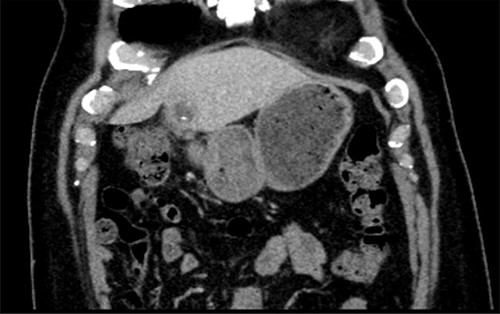

A 56-year-old man presented with a 2-day history of epigastric pain, leucocytosis and raised C Reactive Protein (CRP). A computed tomography (CT) scan revealed evidence of a 4.2 × 2.5 cm abscess in the left lobe of the liver (Segment III), with a linear radio-dense foreign body seen within the collection (Fig. 1). There was fat stranding around the pylorus. The patient was treated with antibiotics in his local hospital and a trial of aspiration revealed purulent fluid. An oesphagoduodenoscopy (OGD) was normal with no evidence of foreign body or inflammation in the stomach.

The patient was transferred to our Hepatopancreaticobiliary (HPB) unit. On arrival, he was clinically well and asymptomatic. A repeat CT scan showed a persistent collection in the liver. On further enquiry, the patient revealed that a few weeks earlier as he had a transient episode of choking and discomfort whilst eating fish.